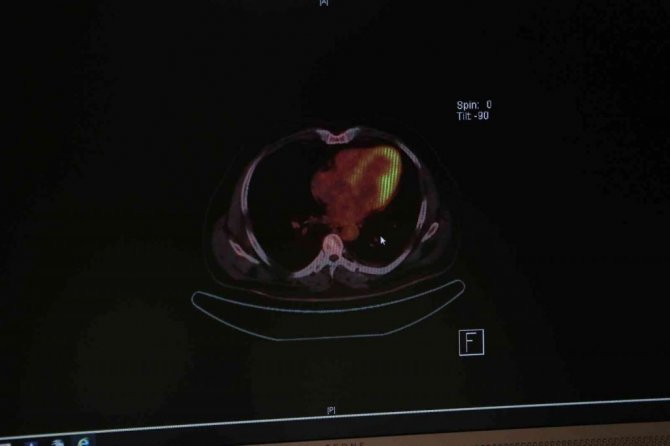

Akciğer kanserinin dünyada en sık görülen kanser türü olduğunu ve ölüme yol açan kanser hastalıkları arasında da ilk sırada yer aldığını belirten Prof. Dr. Çalıkuşu, "Akciğer kanseri erkeklerde en sık ölüme neden olan birinci kanser, kadınlarda ise ikinci kanser türüdür. Dünya genelinde yapılan araştırmalar gösteriyor ki akciğer kanseri genellikle hastalığın metastaz yaptığı dönemde yani diğer organlara sıçradığı evrede teşhis ediliyor. Bu evrede cerrahi şansı yok denecek kadar az oluyor, hastalığın medikal tedavi oranı ise giderek düşüyor" diye konuştu.

Akciğer kanserinin çoğunlukla 55 yaş ve üzerinde görüldüğünü belirten Prof. Dr. Züleyha Çalıkuşu, "Akciğer kanserinde önemli risk faktörleri vardır. Bunların başında; sigaraya başlama yaşı ile sigarayı kullanma sıklığı ve kanser yapıcı maddelere maruz kalma sayılabilir" dedi.

"50 yaşın üzerinde bulunan ve en az 20-30 yıldır günde bir paket sigara içenler ya da 10 yıldır iki paket sigara tüketenler, risk grubunda yer alıyor. Bu kişiler için düşük doz bilgisayarlı tomografi çekimi, akciğer kanseri tarama yöntemi olabilir. Erken evrede tanı alan hastalarımız tam tedavi şansına ulaştığı için bu kontroller ihmal edilmemeli. Ne yazık ki koronovirüs pandemisi döneminde hastaneye gelmekten korkan hastaların erken tanı şansı azaldı. Bu sorunu sıklıkla yaşadık. Erken tanı sayesinde kanserin ilk evresinde olan hastalarımız tedavi şansı buldu. Ancak geç tanı alanların tedavisi de gecikti."